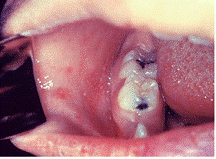

Рисунок 6. Ангина Симановского- Венсана